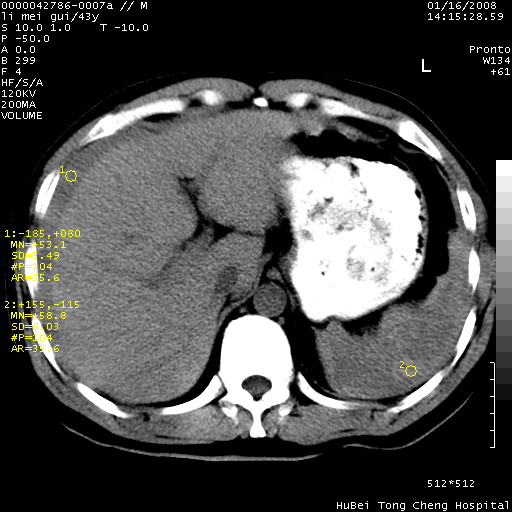

| 患者,男,43岁。突发腹痛2小时,面色苍白,难以平卧。自述近期无明确外伤史,为摩托车驾驶员。 腹部b超检查:脾脏中上极回声异常,肿瘤待排。 临床诊断:腹痛原因待查。 上中腹部ct轴位平扫+增强扫描(层厚10mm,螺距1.0,重建间隔10mm),图像如下: ![]() ![]() ![]() ![]() ![]() ![]() ![]() ![]() ![]() ![]() ![]() ![]() ![]() ![]() ![]() ![]() ![]() ![]() ![]() ![]() ![]() ![]() ![]() ![]() ![]() ![]() ![]() ![]() ![]() ![]() ![]() ![]() ![]() ![]() ![]() zrs发言:支持脾破裂 wwp发言:支持脾破裂并腹水。 xulianj发言:脾脏肿瘤破裂可能性大 zsl6918发言:不像肿瘤出血,考虑还是与外伤后引起的慢性出血有关 zzyy发言:平扫见肝周及脾周积液,脾内密度不均。脾内肿瘤较少见。还是外伤性脾破裂。 沈丘东方医院发言:脾门区一个不均匀强化病灶与其周液体相连多考虑脾占位破裂出血 yixianman001011发言:脾破裂并腹水是可以肯定的,具体原因多以肿瘤性破裂出血,脾脏淋巴瘤可能性大. 结果: 术后,经详细询问患者,其仔细回忆:一月前骑摩托时左侧腰部与别人有“轻微”触碰,因责任在自已,当时又无明显不适,未引起注意。 临床术后诊断:脾破裂并失血性休克(1.外伤性迟发性脾破裂。2.脾脏肿瘤破裂?) 术后标本病检:脾破裂并出血,未见明显肿瘤成份。 原贴地址:http://www.radinet.com.cn/forum_view.asp?forum_id=4&view_id=34070 |